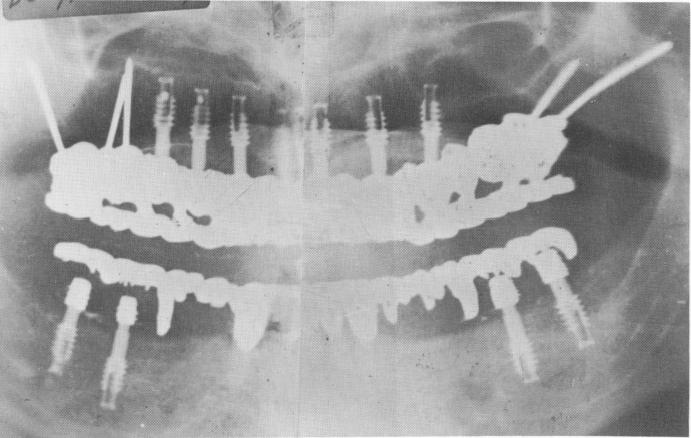

Fig. 10-264. A Panorex shows the seven vent-plants, triplant, and biplant. The lower jaw was also reconstructed with four vent-plants.

The mixed implants supporting the prosthesis, their placement, and their relationships are clearly visible in Fig. 10-264.

1 Panorex showing seven ventplants, triplant, and biplant